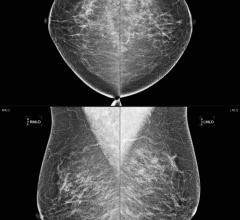

Despite decades of progress in breast imaging, one challenge continues to test even the most skilled radiologists ...